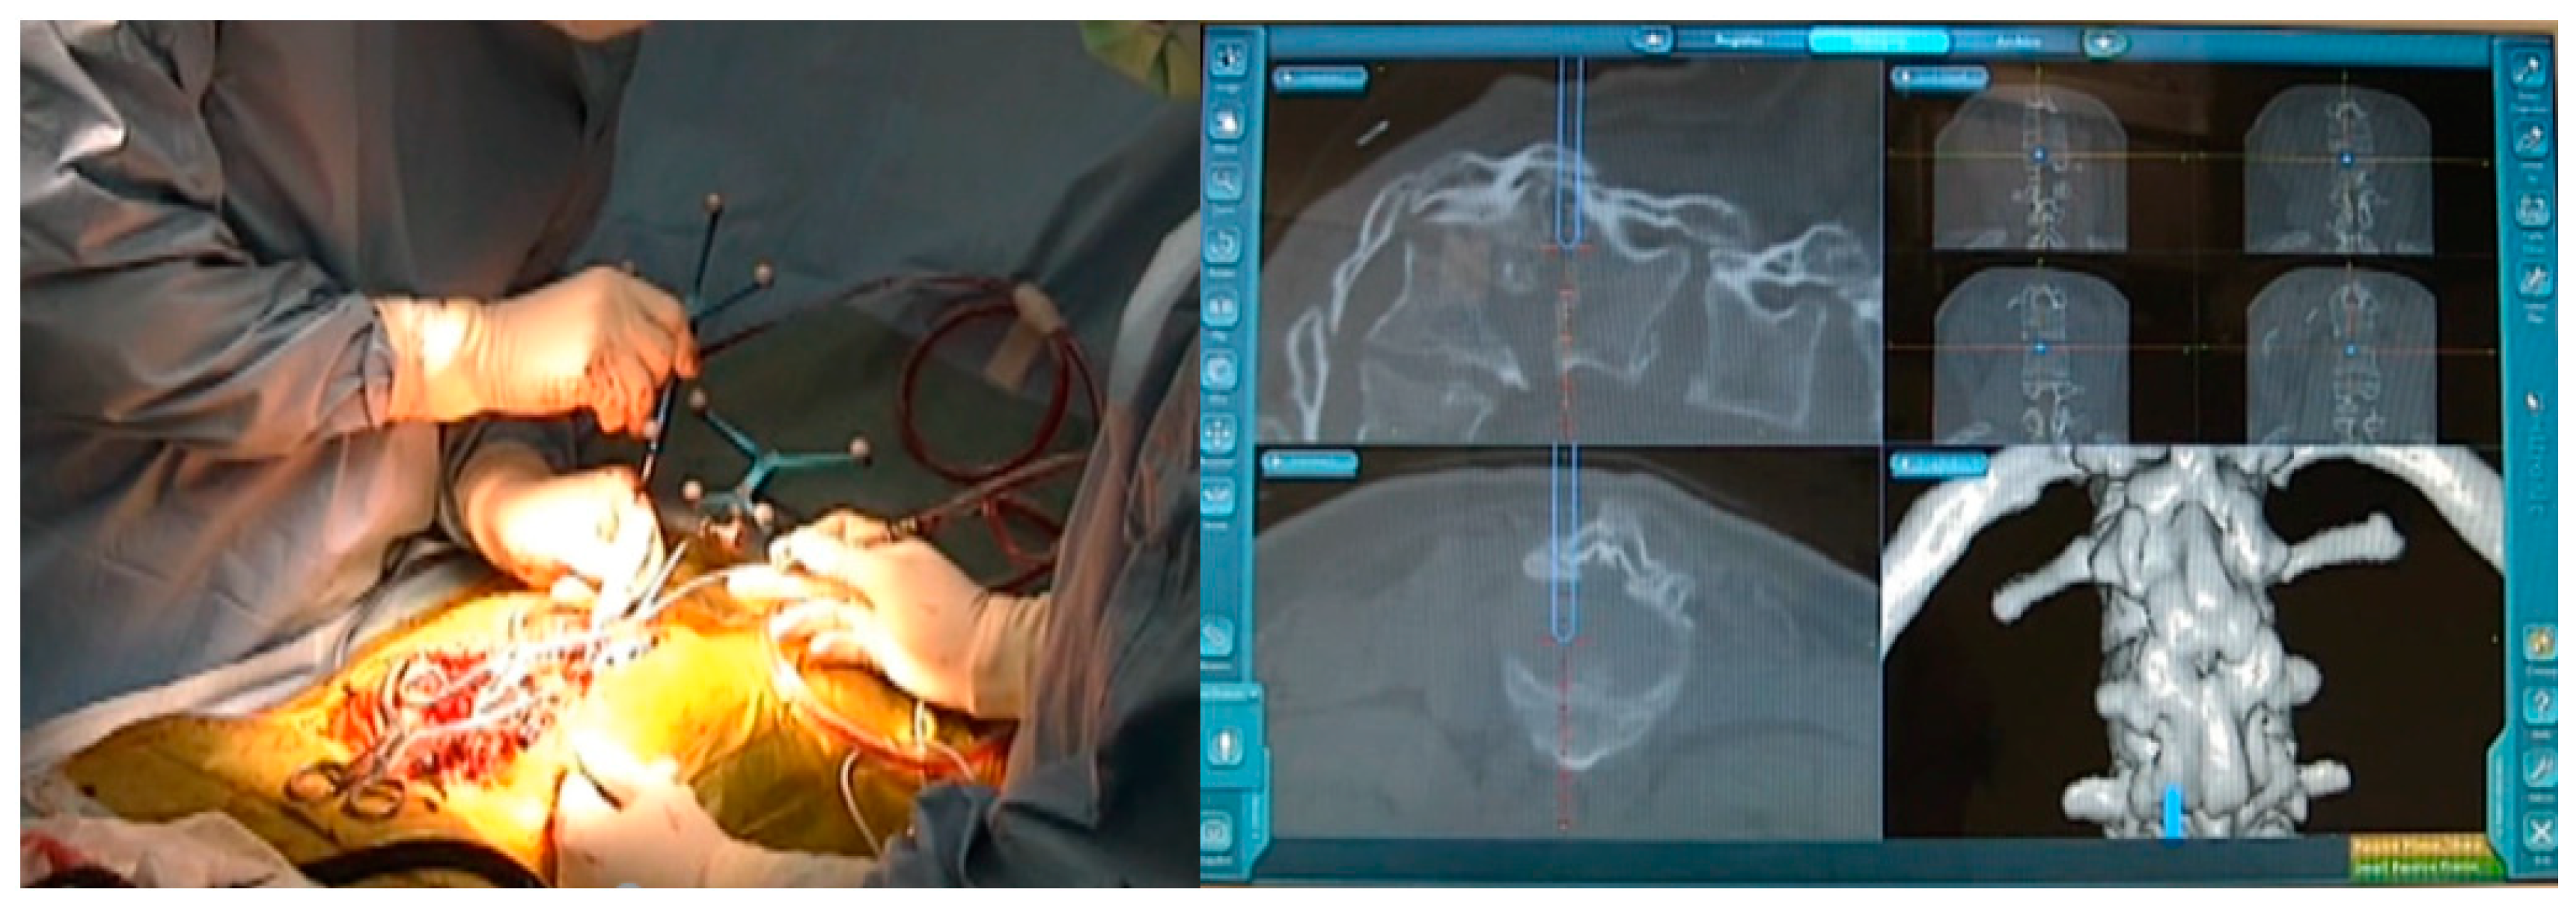

3.1. Case 1—16-Year-Old Girl, Achondroplasia, Thoracolumbar Kyphosis 126°

3.1.4. Surgery